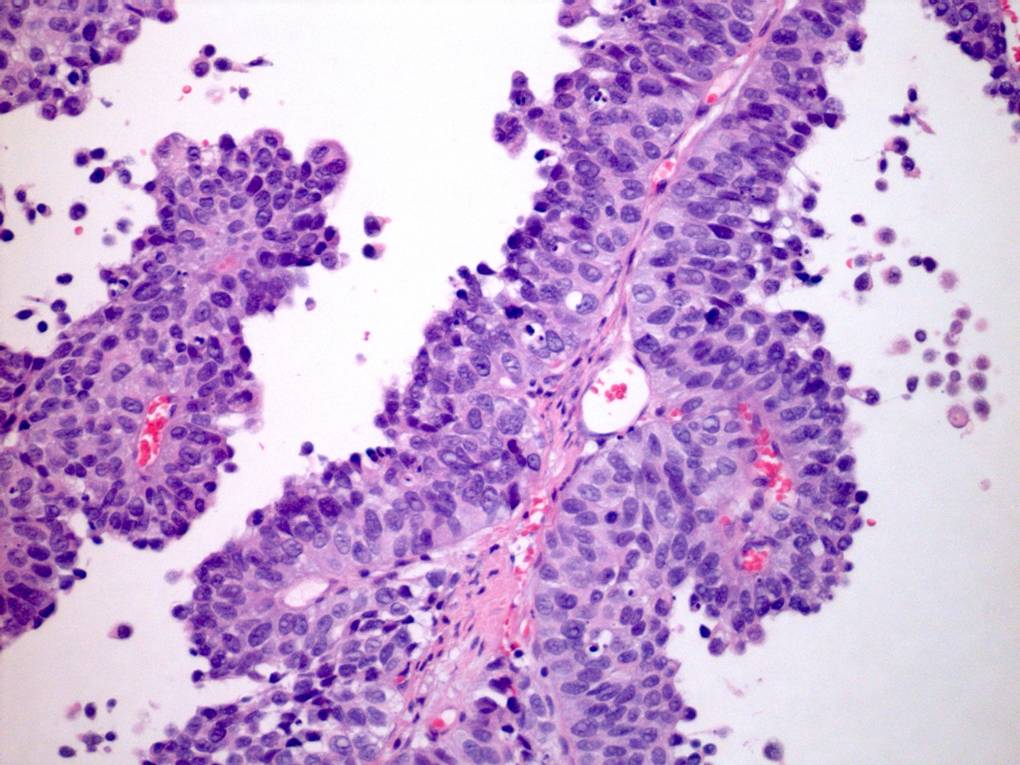

Consensus grade: High-grade papillary urothelial carcinoma (HG-PUC)

Case description (by case creator):

65 year old male. From TURBT. Diagnosis illustrated = high grade papillary urothelial carcinoma